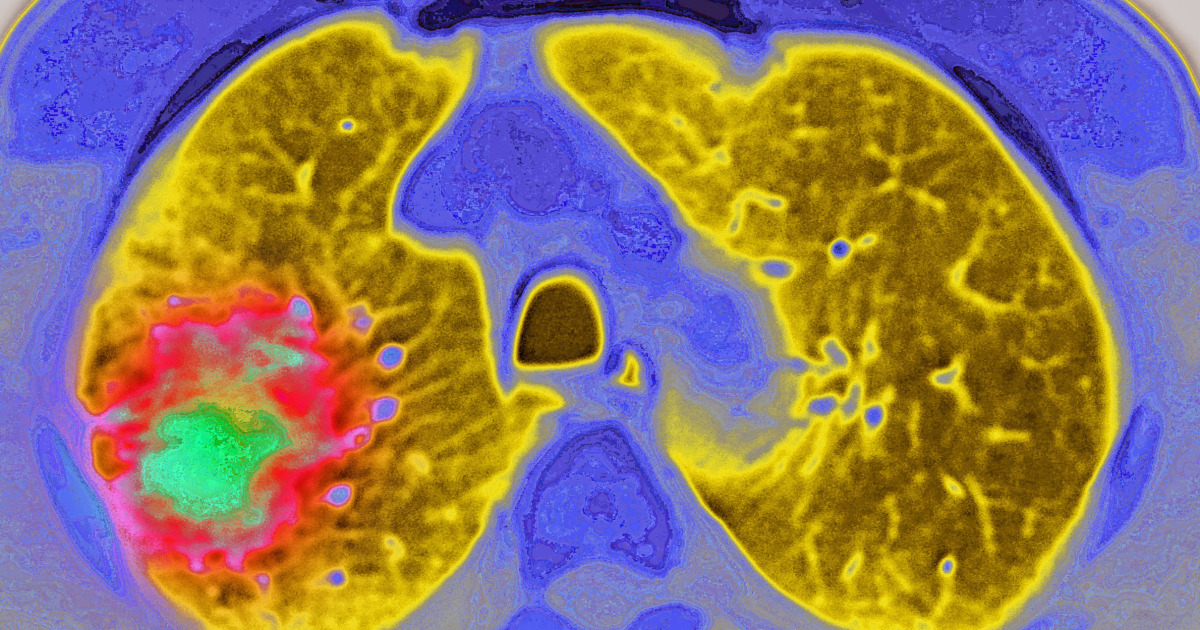

Pfizer anticipates its lung cancer drug Lorbrena will surpass $1 billion in annual sales by 2030, driven by strong five-year clinical trial data showing significant disease progression-free survival rates in patients with ALK-positive advanced lung cancer. The drug, which outperforms Pfizer's earlier treatment Xalkori, has shown particularly promising results in patients with brain metastases and is expected to see substantial market growth, especially in China.